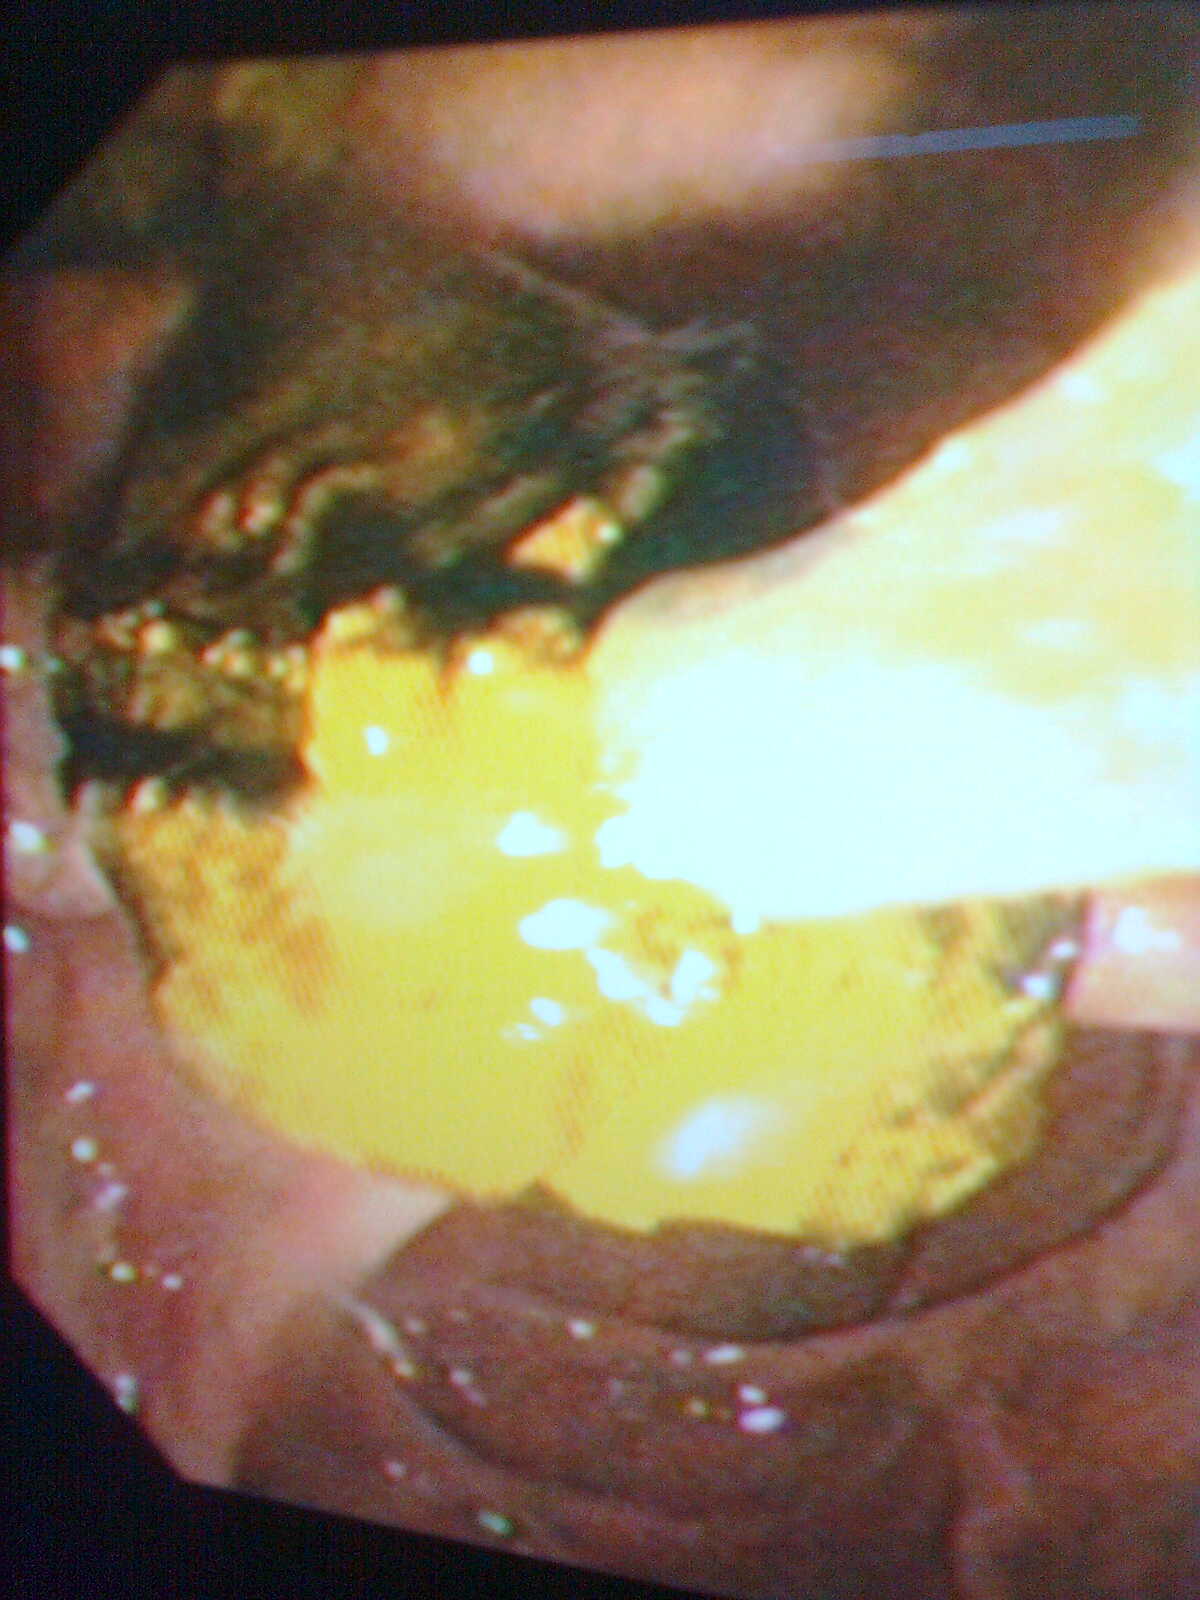

(四)、内镜下胃、肠道息肉切除术

胃、肠道息肉是重要的癌前病变,胃镜、肠镜检查一旦发现有胃、肠道息肉,就应该切除;否则就有癌变的可能。在胃镜或肠镜监视下行息肉电凝切术,是治疗息肉的最佳办法,创伤小,效果好。消化科拥有先进的德国爱尔博(ERBE)高频电凝切仪,配合电子胃镜、肠镜,行息肉电凝切术,效果良好。

肠道息肉切除术后